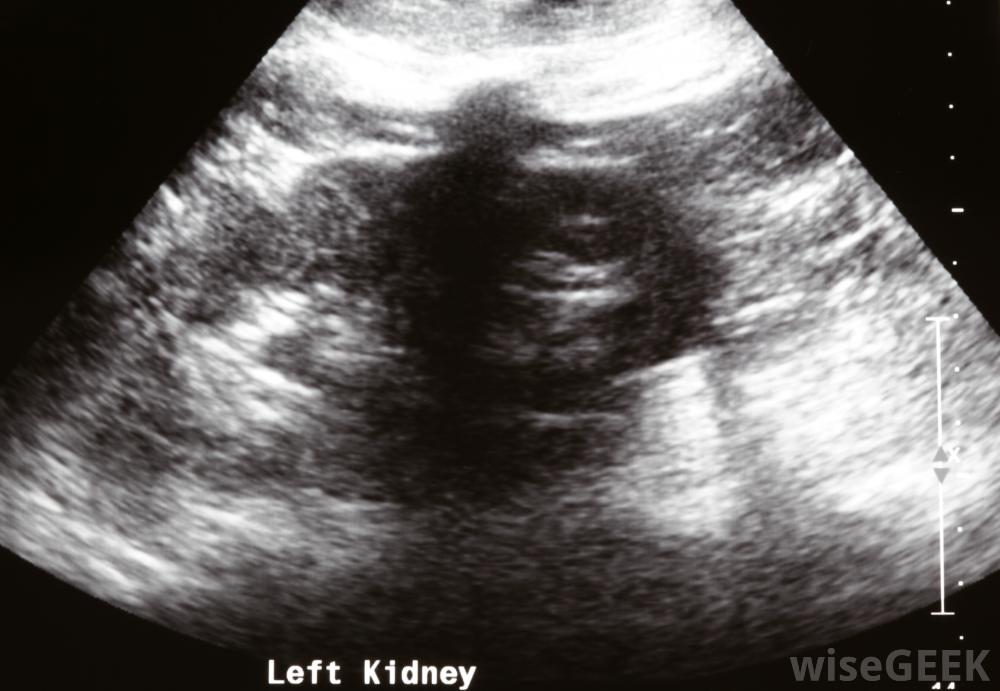

在超聲波檢查中,技術人員將一種被稱為傳感器的手持設備應用于需要評估的身體部位。傳感器發出高頻聲波,當它們接觸內部結構時,這些聲波會反射回設備。監視器上會形成黑白圖像,根據回聲的強度,放射科醫生稱來自高反射表面的較亮圖像高回聲,而反射較弱的區域則顯示為較暗的區域,并被稱為低回聲

腎臟的低回聲病變可能導致嚴重的腹痛和背痛

腎臟低回聲病變可能是常見的,良性腫瘤稱為纖維腺瘤或乳腺囊腫。如果病變不正常或不符合某些標準,例如一端有深色陰影,含有鈣化點,或顯示其他一些不尋常的、明確的特征,衛生保健人員可能會懷疑是癌癥。隨后的檢查可能包括針活檢包括用針頭和注射器提取細胞。肝臟病變:肝細胞腺瘤,也稱為肝細胞腺瘤,和肝血管瘤都是良性腫瘤,在超聲上可產生低回聲病變。這些腫瘤通常被切除,尤其是在引起不適的情況下,為了避免它們變成癌細胞的風險。飲酒、肥胖和糖尿病是脂肪沉積的一些常見原因,這些脂肪沉積在肝臟上表現為病變;根據病因的不同,有可能逆轉這些沉積。肝癌也可能表現為低回聲;通常,計算機斷層掃描(CT)是用來正確診斷肝癌的。前列腺病變:前列腺癌在超聲上幾乎總是表現為低回聲病變。醫療人員可以通過血液測試、針活檢或進一步的成像研究來診斷惡性低回聲病變。細菌、真菌,或者病毒感染可以導致前列腺炎,也可以表現為低回聲病變。甲狀腺病變:大多數甲狀腺病變是良性的,非常常見。患有甲狀腺過度活躍或活動不足的人會出現甲狀腺腫大,通常稱為甲狀腺腫該區域的低回聲病變可能只表明甲狀腺腫大或感染。自身免疫性疾病也會影響甲狀腺,導致橋本氏病。甲狀腺癌可以是低回聲的,通常很容易治療。腎臟病變:低回聲病變也可以出現在腎臟上,可能表明腎結石或腎囊腫一樣常見的東西。都會引起腹痛,通常需要治療。腎細胞癌或腎癌,也可能表現為低回聲病變,需要額外的放射學檢查才能正確診斷。

在超聲檢查過程中,技術人員將一種稱為傳感器的手持設備應用于身體以評估腎臟。